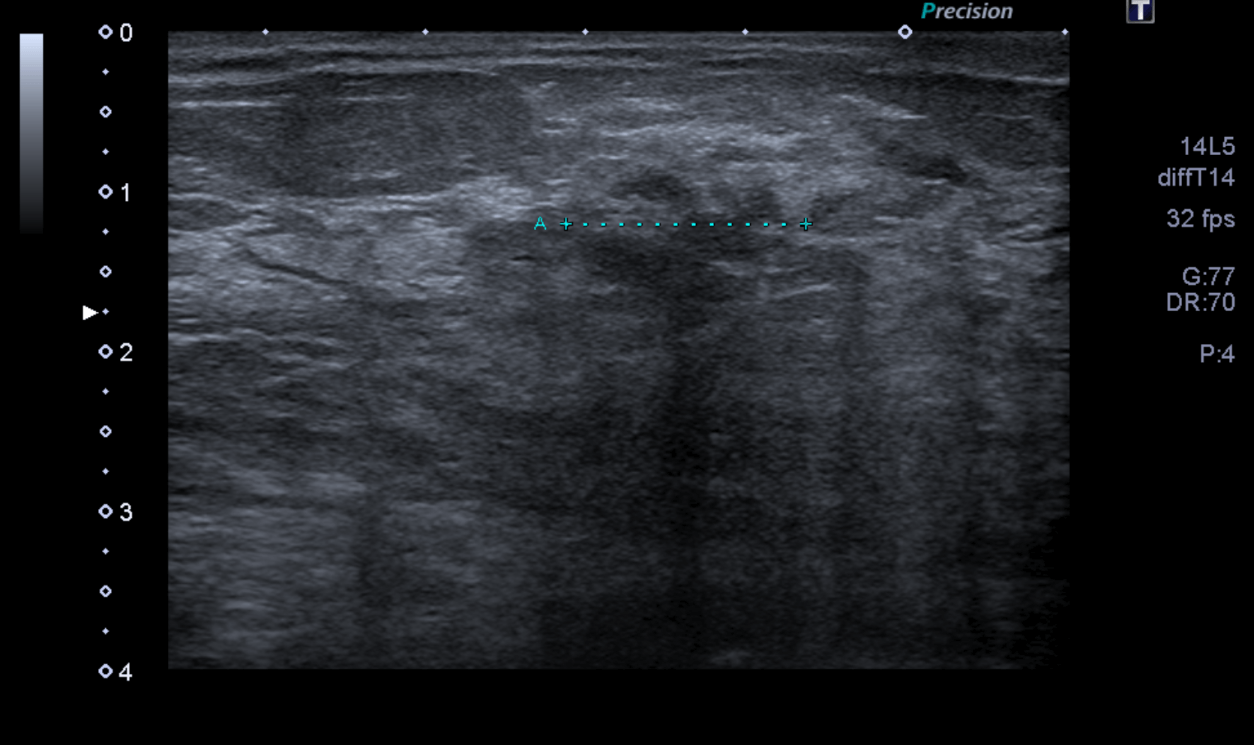

La masse est retrouvée en échographie et mesure 20mm. L’IRM donne une masse volumineuse.

Avec un score très élevé, l’IA aurait pu alerter d’autant plus le radiologue initial.

Biopsie : CCI grade 3